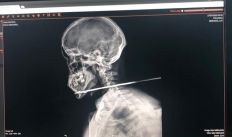

Homem tem pescoço perfurado por flecha ao tentar cruzar fronteira entre Guiana e Brasil

Com a flecha cravada no pescoço, vítima, que é brasileira, ainda conseguiu pedir socorro no hospital de Bonfim, ao Norte de Roraima